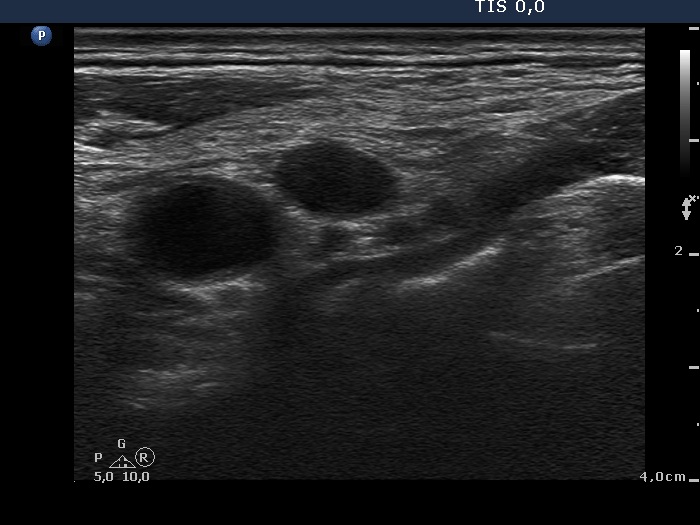

Ultrasonography: The thyroid was intact. There were multiple nodes in both supraclavicular regions. The nodes presented an absolutely irregular shape and border. They contained numerous hyperechogenic circumscribed areas.